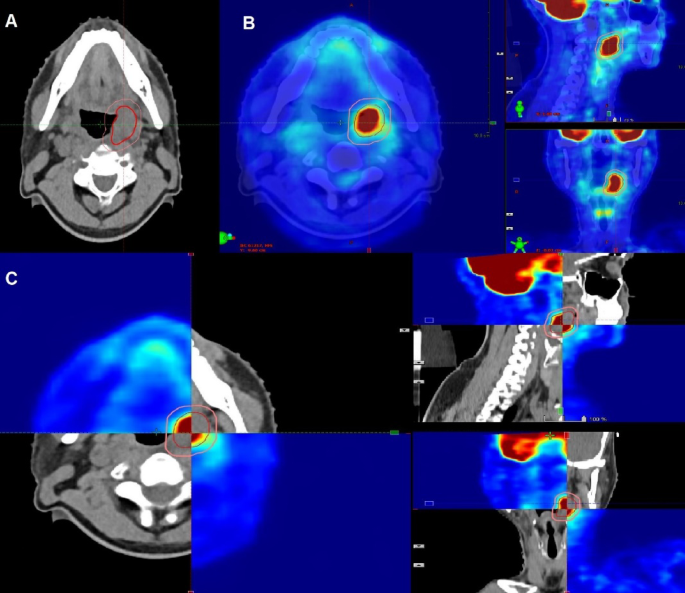

Following dental prophylaxis, patients underwent RT planning, including a contrast-enhanced CT scan in the treatment position with laser alignment to the markers. Head and neck CT scans, with 2.5–3 mm slices, were taken using a helical CT scanner up to the carina level after intravenous contrast injection. CT images were transferred as DICOM files to the contouring workstation, Eclipse planning system. The OARs were contoured per Radiation Therapy Oncology Group (RTOG) contouring guidelines. For definitive RERT, gross tumor volume (GTV) was mapped based on clinical findings, radiological imaging, and direct/indirect laryngoscopy findings, with PET CT assisting in GTV delineation. The PET CT, initially used for disease diagnosis, guided target delineation (Fig. 1). The DICOM files underwent rigid registration with CTsim as the target image and CTpet as the source image, initially auto-matched and manually refined. Using the PET adaptive threshold technique, the SUVmax of the tumor is set for contouring purpose. Now the PET components were overlaid on CTsim to define disease, using a 40% SUVmax threshold algorithm for GTV delineation, followed by slice-by-slice validation to include suspicious, contrast-enhancing regions. A 5 mm planning target volume (PTV) margin was standardly added to the GTV in re-irradiation.

For adjuvant RERT, the preoperative PET CT was similarly fused with CTsim, involving the same matching procedure (Fig. 2). The auto-contoured GTV volume was compared to the post-operative bed (CTV) contour on CTsim to ensure inclusion of suspicious volumes, subsequently receiving a 5 mm PTV margin.